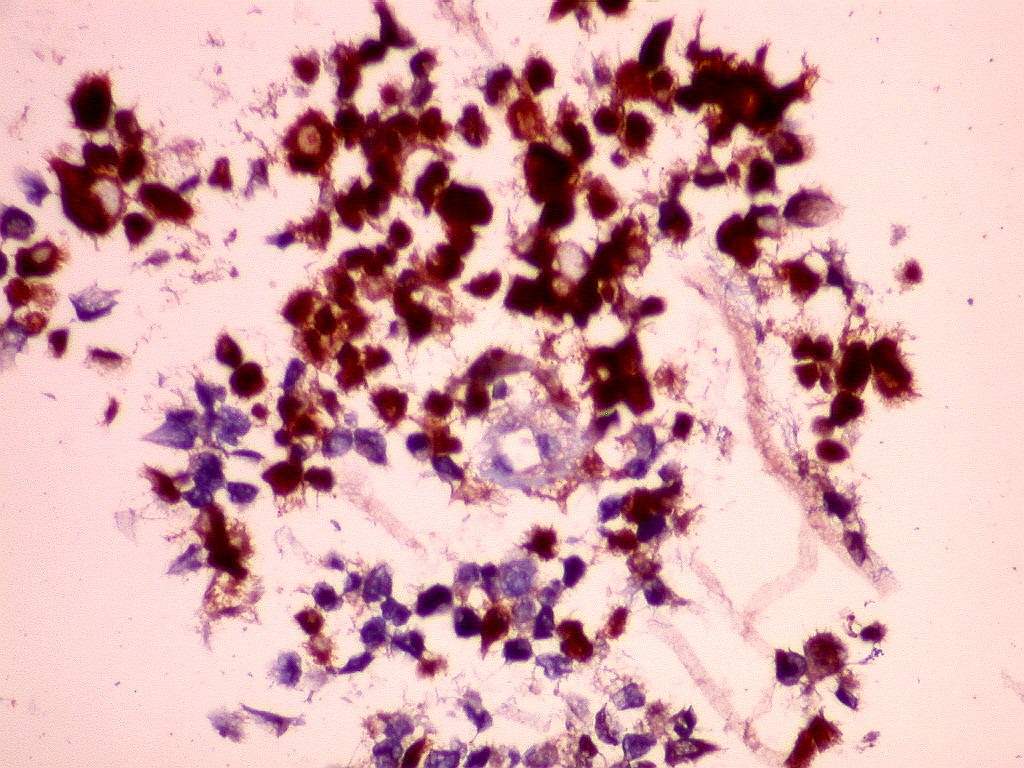

MAP2.   Microtubular associated protein,  marcador de diferenciação  neuronal. Universalmente positivo nas células deste ATRT.  Folículo linfóide  negativo (controle  interno).  Marcação é citoplasmática, na periferia do citoplasma.  Corpúsculo rabdóide negativo.  Para mais sobre MAP2, clique.